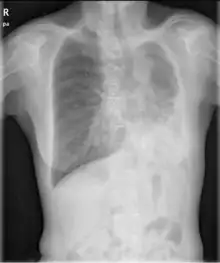

| Left tension pneumothorax with a large, well-demarcated area devoid of lung markings with tracheal deviation and movement of the heart away from the affected side. |

Tension pneumothorax

Tension pneumothorax is an emergent condition in which air gets trapped in the space between the chest wall and the lung. This space is referred to as the pleural space. Because air can't escape from this space, the pocket of air grows larger and larger which results in collapse of the lung closest to the pneumothorax. Forces are transmitted to the mediastinum and effectively "push" the mediastinal structures to the opposite side of the chest. [5]